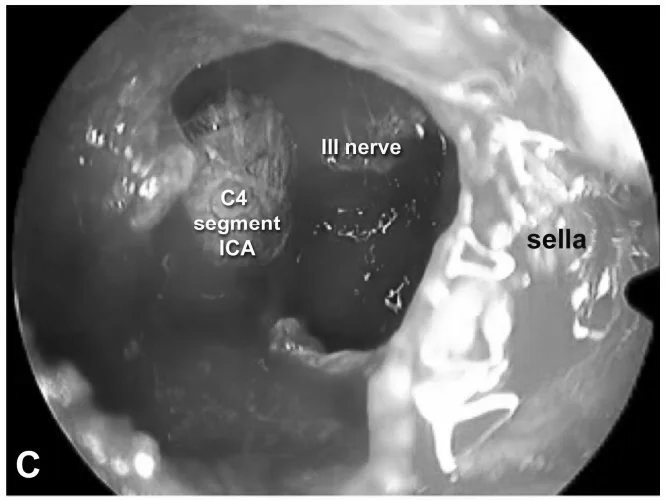

INC福教授为Estelle采用标准经鼻经蝶窦入路内镜手术,随后通过移除海绵窦颈内动脉前段上的骨质进行外侧扩展术野。

内镜下经内侧三角入路